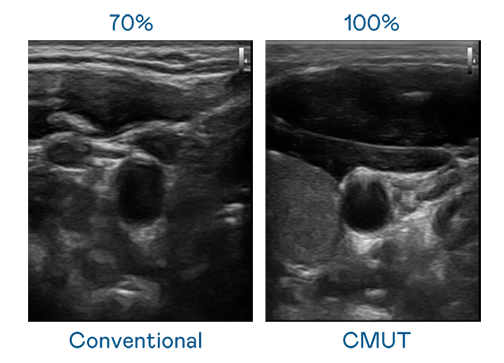

CMUT 技术是一种用电容式微机电元件来产生超音波讯号的技术。与传统 PZT 压电式技术相比,CMUT 频宽增加 30%,更宽频的超音波讯号让影像解析度大幅提升,是实现高影像品质医疗超音波扫描、促进精准医疗发展的关键技术。

大频宽带来超清晰影像

超音波影像的解析度高低,首先取决于探头能发出的讯号频宽。MK体育官网 CMUT 可提供高清晰的超音波讯号,提供高频宽、高灵敏度、影像纹理细节更高的超音波影像,协助医护人员缩短影像判读时间及利用精准的医疗影像进行诊断。